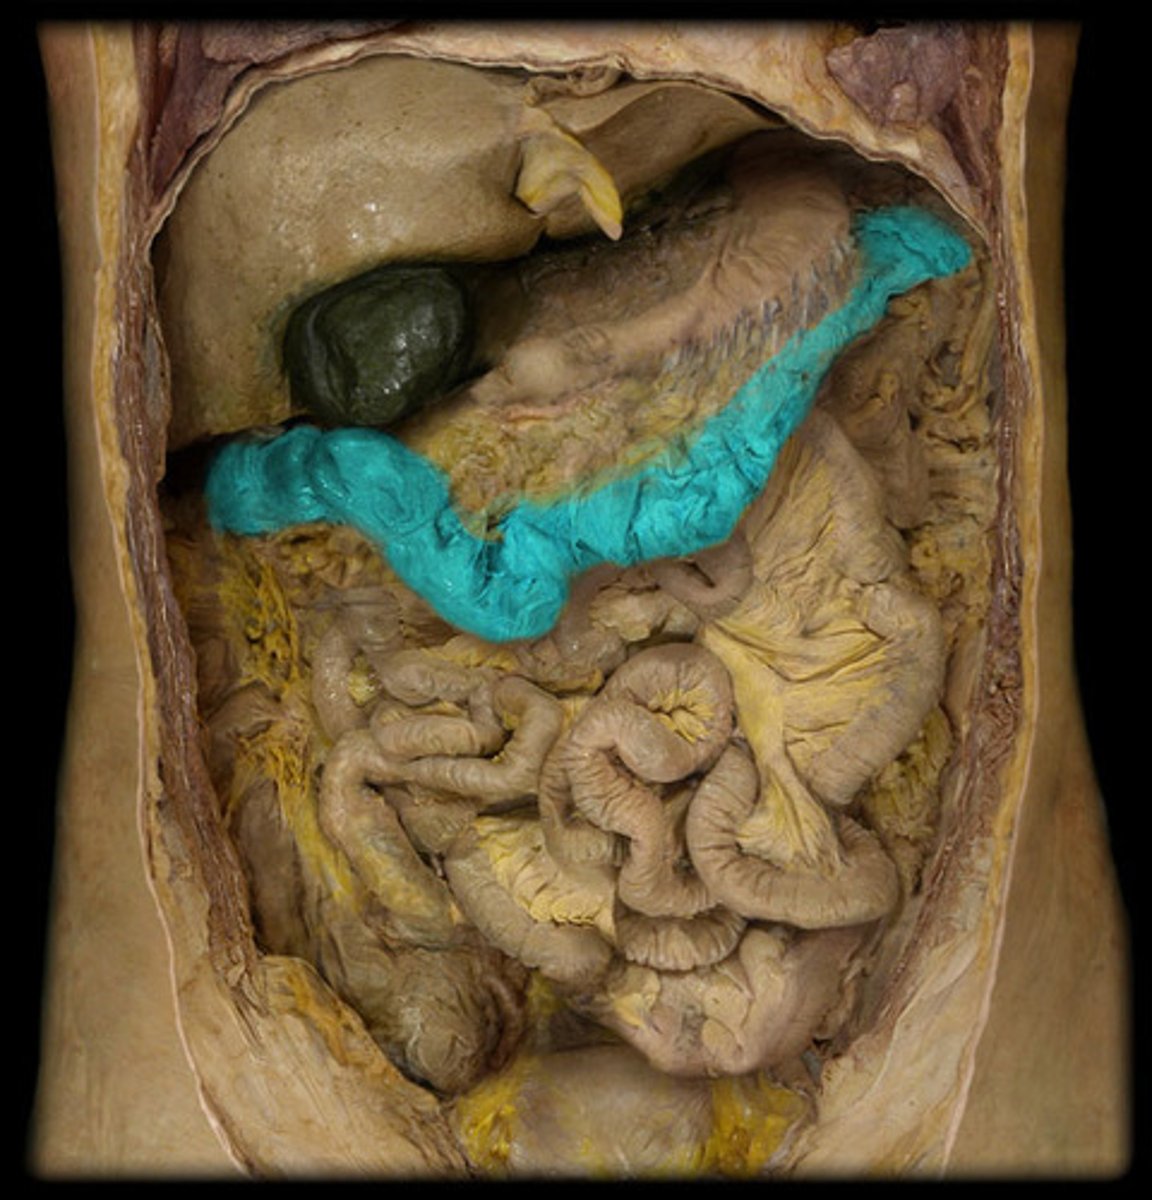

Duodenum

Transverse colon